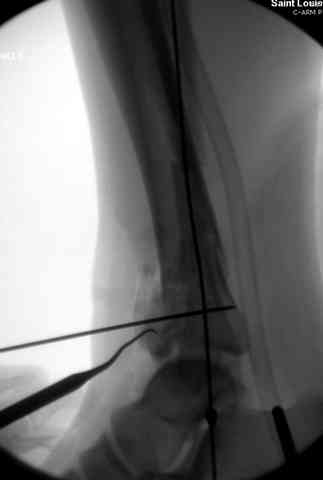

Открыто или закрыто - это уже зависит от опыта и

наличия материала. Минимальным аппаратом Илизарова или одним из Contoured Medial или Antero-Lateral Locking Plate из лимитирванного доступа не имеет значения, но самое главное необходимо добиться репозиции сустава.

Первичная пластина или интрамедуллярный фиксатор на малоберцовую зависит от характера перелома, косые и многооскольчатые пластинами, а поперечных можно интрамедуллярными фиксаторами. Восстановленная длина малоберцовой служит ориентиром и помогает определению высоты большеберцовой во время восстановления.

Переломы пилона сопровождаются ударом со сминанием в метафизарной части большеберцовой, то есть со значительной потерей костного объема.

При репозиции суставных поверхностей образуются полости в метафизарных отделах, без заполнения их

структуральными элементами невозможно предохраниться от посттравматической деформации. Латеральная колонна удерживается малоберцовой поэтому голень деформируется в варус.

Здесь выставлена пара случаев перелома пилона, оба

случая леченные этапным наружным фиксатором.